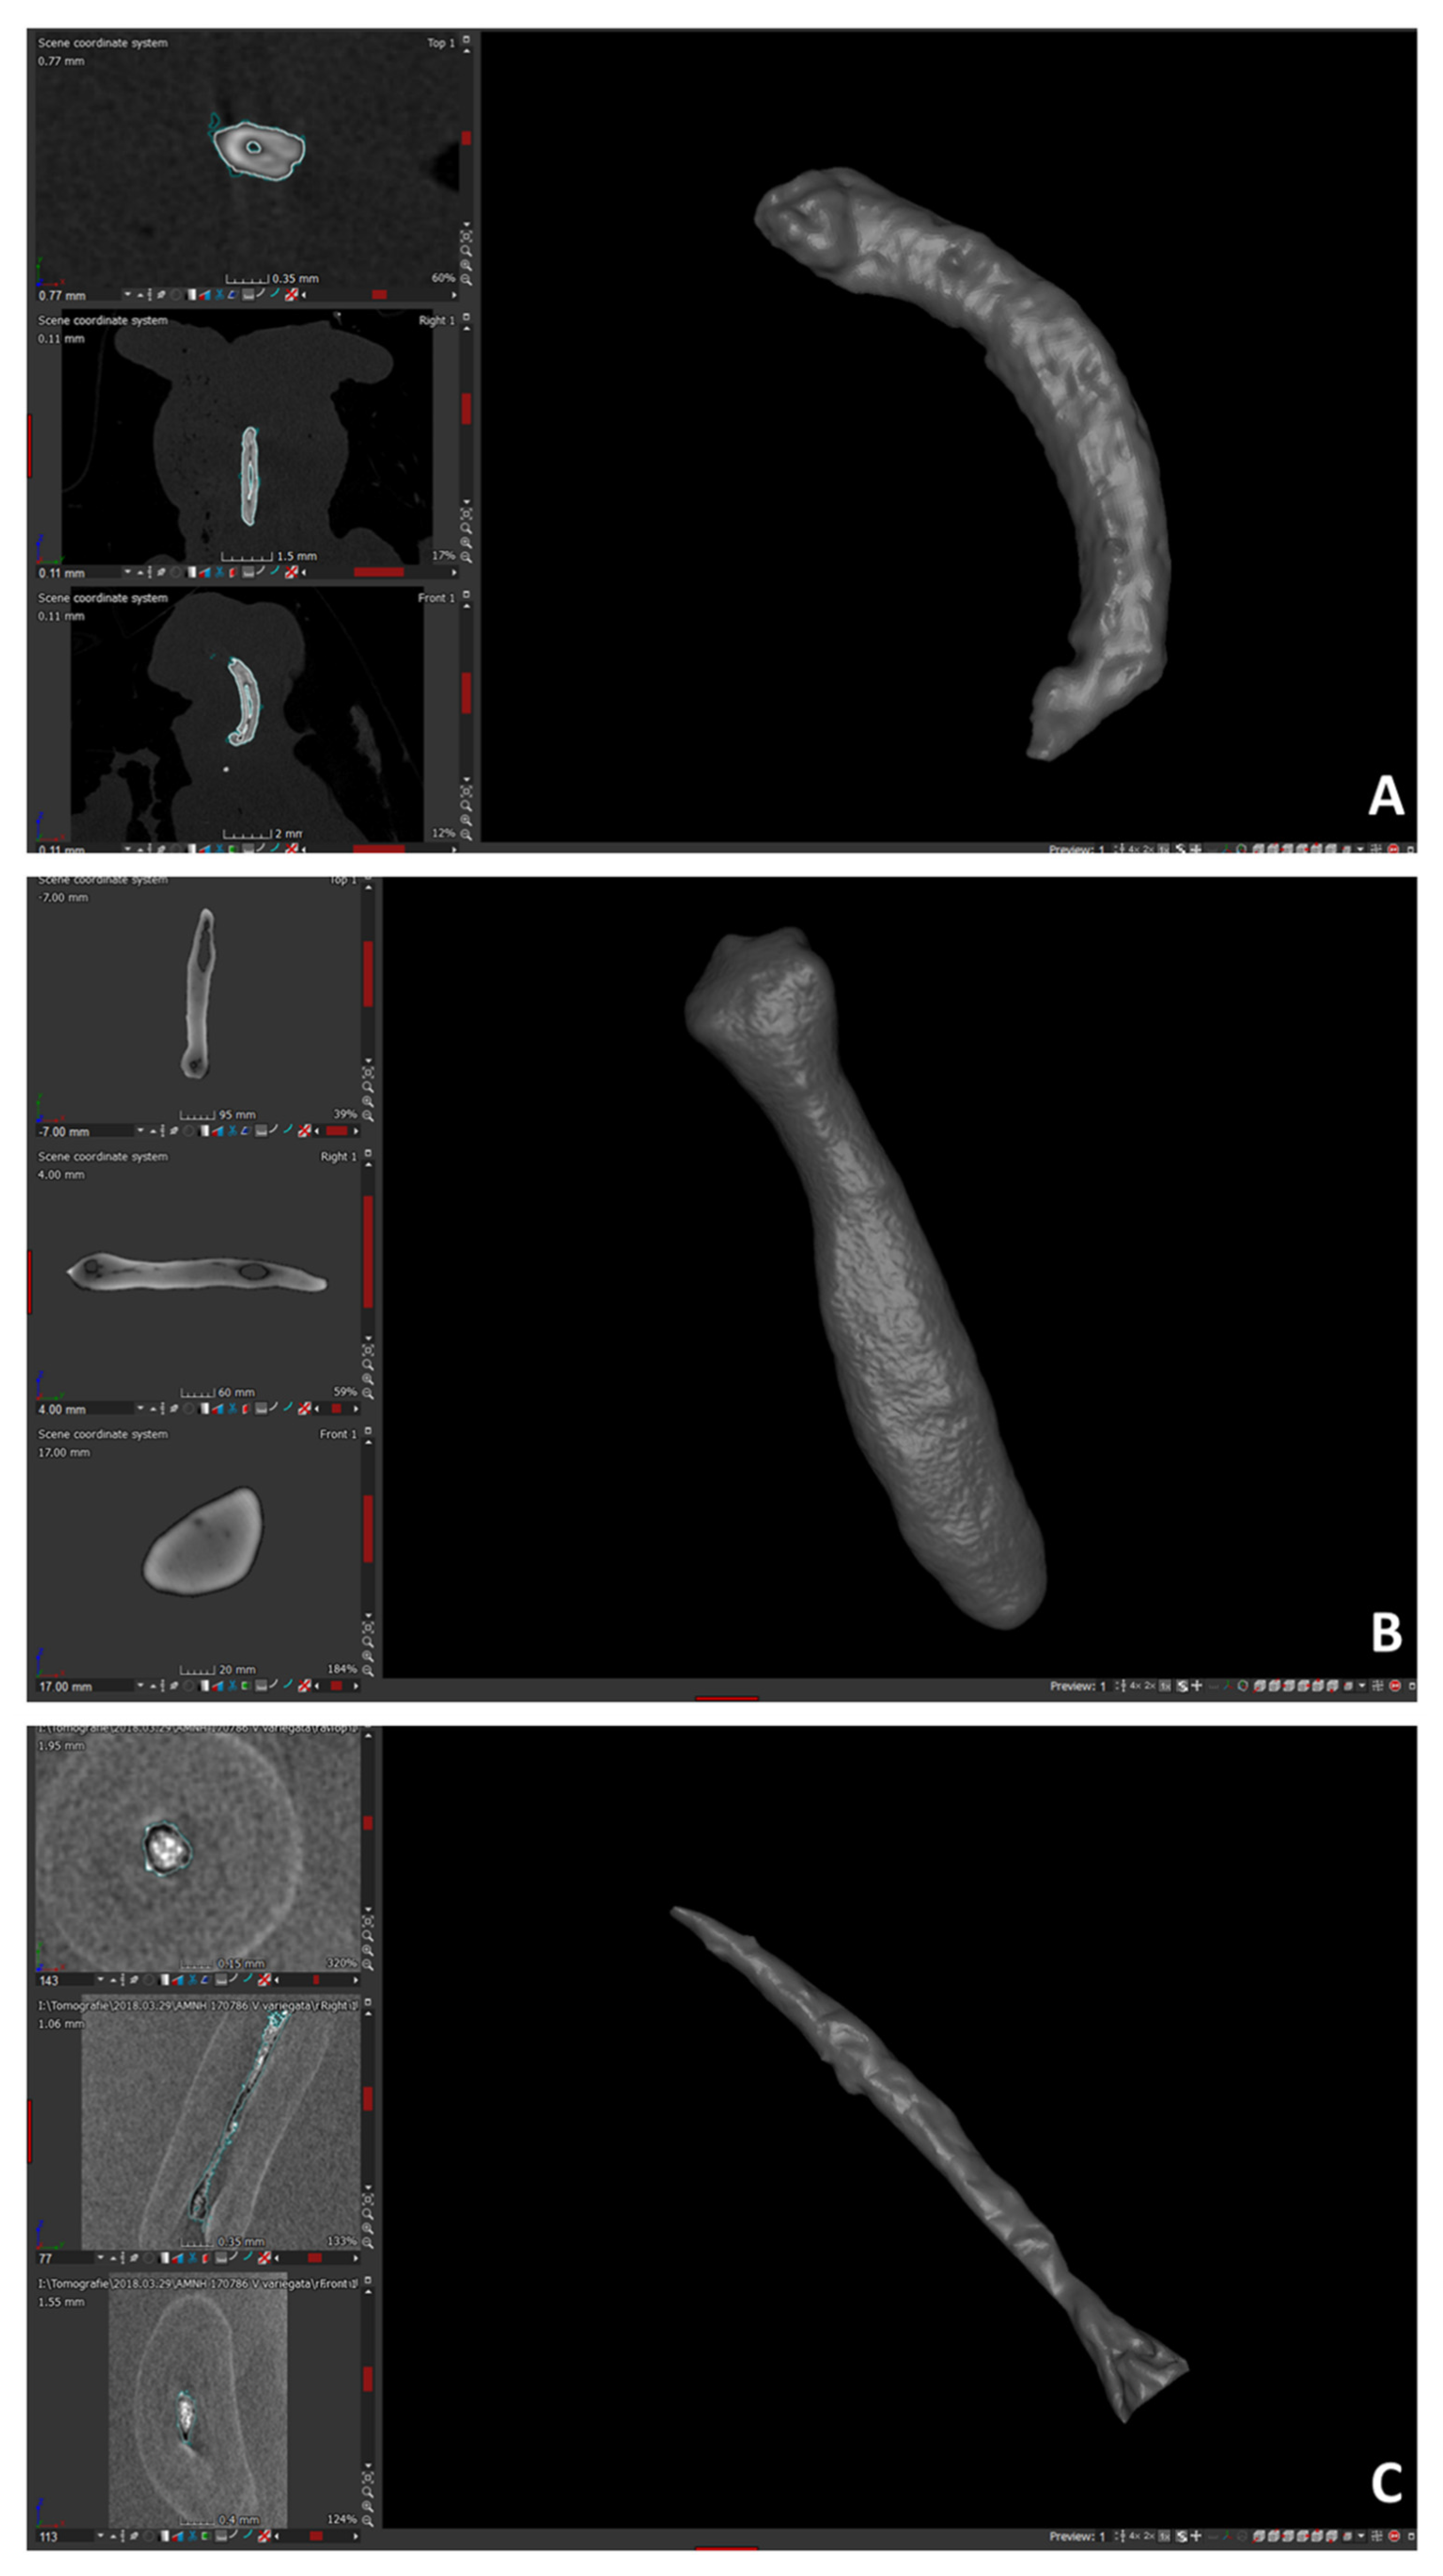

- The product of segmentation (see ‘Anatomical data collection and 3D morphological data acquisition’ section) was extracted either as a 3D polygonal volumetric model (file format: ply) or mesh. The polygonal models were post-processed with Amira and Geomagic Studio 2014 software.

- The total number of polygons was taken down to 250,000 in Amira, and the extracted surface, loaded into Geomagic Studio 2014, was corrected by deleting (automatically and manually) computational errors in the mesh, such as non-manifold edges, self-intersections, highly creased edges, spikes, small components, small tunnels, and small holes. Only the external surface of bones was kept, by emptied 3D models, to avoid anatomical non-homologies in the bone’s internal structure. In addition, each baubellum length was measured by using the distal and proximal ends of the bones as reference points. The length was recorded 3 times by the same operator (FS), and the mean was calculated.

- The mesh was converted to a point cloud with Meshlab software, and the total number of points making up the cloud was set to 100,000.